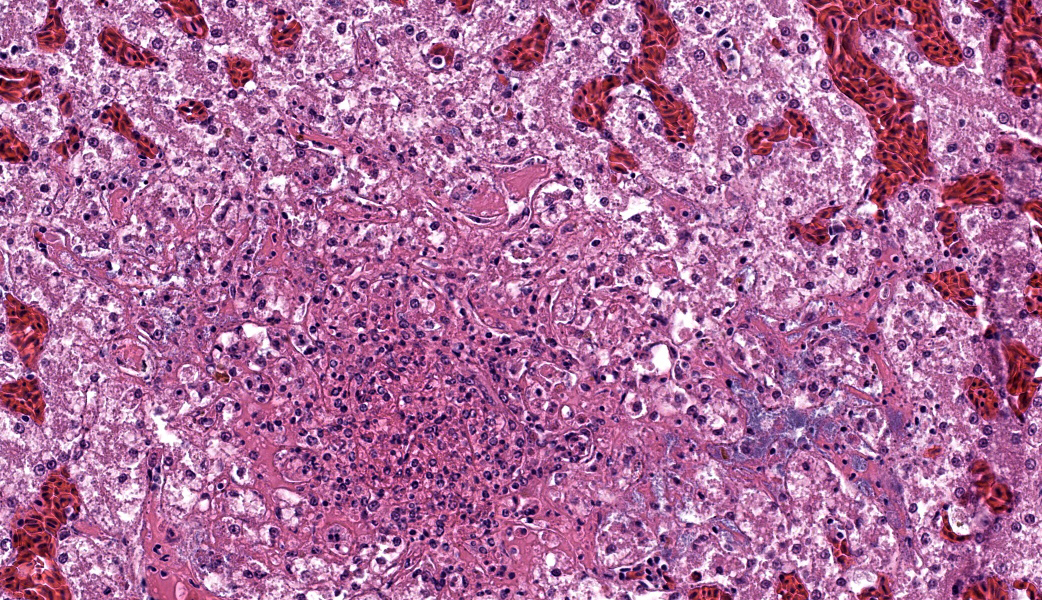

Microscopic Description: The liver has multiple random foci of necrosis that are filled with necrotic debris, fibrin, variable numbers of intact and degenerate heterophils and macrophages, and variable numbers of Gram-negative coccobacilli. There are multiple sinusoids that contain coccobacilli with small numbers of sinusoids that contain fibrin thrombi. The hepatocytes adjacent to the sinusoids with fibrin thrombi are often necrotic. There are small numbers of perivascular aggregates of lymphocytes.

Liver – Hepatitis, necrotizing, heterophilic and histiocytic, random, multifocal with intralesional and intravascular Gram-negative coccobacilli and sinusoidal fibrin thrombi; etiology Pasteurella multocida.

Liver: Hepatitis, necrotizing, acute, random, marked, with fibrin thrombi and numerous colonies of coccobacilli.